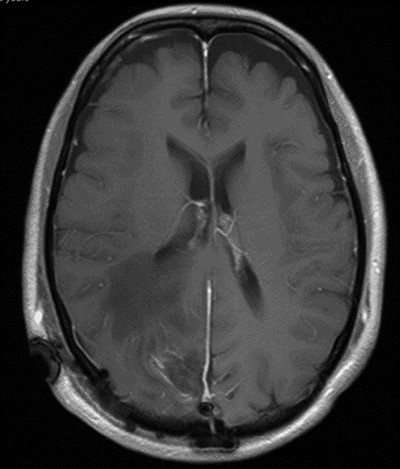

The operation was successful with a post-operative MRI within 48 h demonstrating complete resection of the tumour and resolution of the cystic lesions, but persisting intraparenchymal oedema (Fig. 3). The patient had an uncomplicated two-day stay in a neurosurgery high dependency unit postoperatively before being stepped down to the general neurosurgery ward. She was reviewed by the microbiology team and worked up for the source of infection. Blood cultures, urine cultures, CXR and transthoracic echocardiography were all negative for a source of infection. Intra-operative pus cultures isolated MSSA. The histopathology of the tumour was Meningioma WHO Grade 1 with large areas of necrosis and secondary abscess formation. She was discharged feeling well 5 days later after a satisfactory biochemical and clinical response. She was given a weaning course of steroids and a 6-week course of intravenous ceftriaxone via a PICC line as an outpatient as per microbiology advice. Ophthalmology assessment 3 months after discharge confirmed a left inferior quadrantonopia and preserved visual acuity. Repeat MRI and clinic review 8 weeks later showed no radiological residual tumour or oedema (Fig. 4), and the patient’s limb function recovered completely but had ongoing visual symptoms.

T1 weighted axial MRI postgadolinium enhancement within 48 h post-operatively. Small amount of enhancement within the surgical bed remains. Good resection margins with vasogenic oedema. This may represent a small residual. The rim-enhancing cystic lesions appear to have resolved.